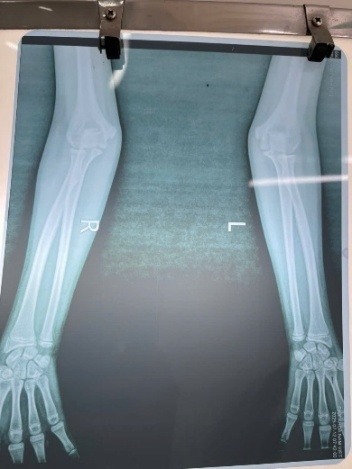

A 7-year-old girl was brought to a local emergency department after falling while playing in a park, landing on her outstretched left hand with the arm abducted. She had pain and swelling of the left elbow with limited motion. She was diagnosed with a soft-tissue injury and immobilized in a plaster splint for two weeks. Three weeks after the injury, she was referred to Thai Binh University Hospital because of persistent elbow pain and marked limitation of motion in the left elbow (Figure 1).

Anteroposterior and lateral radiographs of the left elbow showed a complete anterior dislocation of the radial head relative to the humeral capitellum. The longitudinal axis line of the radius did not pass through the capitellum. No fractures of the radius or ulna were detected, and there was no ulnar bowing. The distal radioulnar joint was preserved. Based on imaging and clinical findings, the McFarland and the Mardem-Bey & Ger criteria for congenital radial head dislocation were not met (Table 1).3